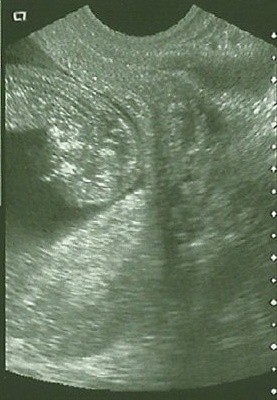

Dagamit, ale przecudna fotka! Znaczy obie, ale buziulka jaka fajniusia! Mój Fasolek wyszedł, jak mały kosmita :-p

Kosmita1a.jpgKosmita2a.jpgKosmita1b.jpg